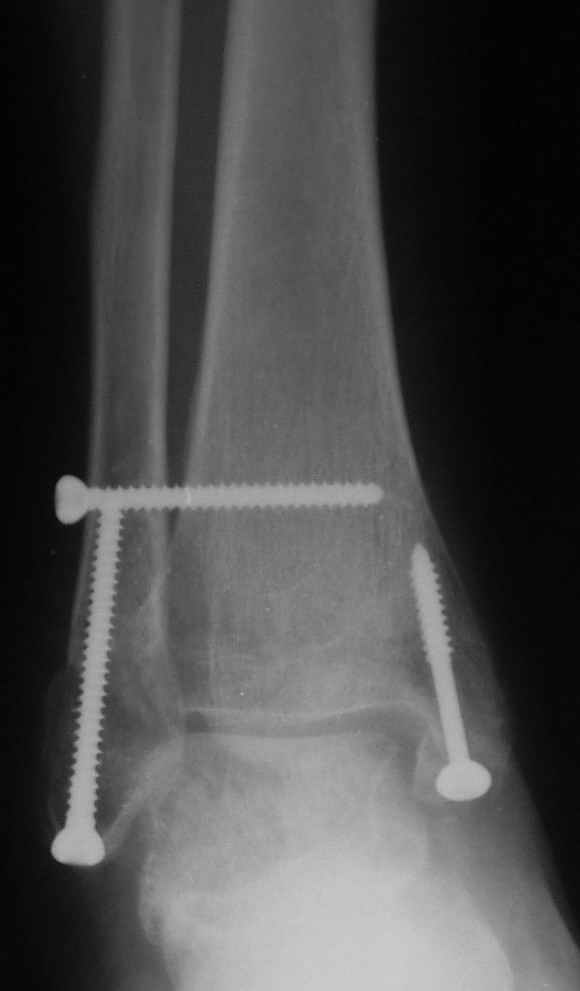

Ниже рентгенограммы

Через месяц

Боковой через месяц

Риторический вопрос - в каком руководстве рекомендован такой способ остеосинтеза наружной лодыжки?

Очевидно, такой результат операции был запрограммирован. При невосстановленной длине и практически нефиксированной малоберцовой кости (этот кортикальный винт - как карандаш в стакане), при неустраненном подвывихе, невправленной и тоже нефиксированной внутренней лодыжке нет стабильной вилки сустава. Если такую операцию сделать даже сразу, а не через 4 месяца, то результат ожидаем

тот же.

Вообще говоря, такое повреждение вполне успешно можно лечить без операции - если 6 недель подержать в гипсовом "сапожке" с хорошо устраненным подвывихом. Вероятное несращение внутренней лодыжки не обязательно компрометирует результат.

Ну а уж если выбран остеосинтез - нначать надо было с репозиции малоберцовой кости с точным восстановлением длины, с фиксацией треть-трубчатой пластиной по задней поверхности. Позиционный винт

избыточен - повреждение практически подсиндесмозное. А если бы

действительно было повреждение синдесмоза - в 4 месяца позиционный винт - не решение. Внутренню лодыжку такую - надо было бы спицами и проволочной петлей. Извините за эти банальности.